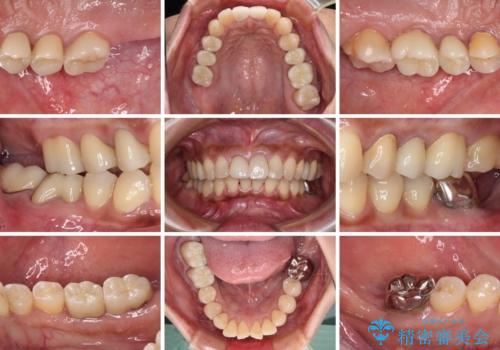

治療中放置してしまった奥歯 セラミック治療

- 奥歯を治療しようと他院で開始したものの、放置してしまったとのことで来院された患者様です。

外れてしまった銀歯や穴の空いた仮歯などあり、適合の悪い被せものと合わせて、セラミッククラウンやセラミックインレーにて治療と行うこととしました。

億劫に感じて治療を先延ばししていたそうですが、始めてみるとスムーズに治療が終わり、早く始めておけば良かったと仰っていました。

他にも加療の必要な歯があるので、定期健診を行いながら再開していく予定です。